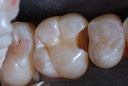

Photos of Clinical Operations

Drs. Peter Kearney, Terry McKay, John St. Germain, and Laurie Vanzella - Mentors